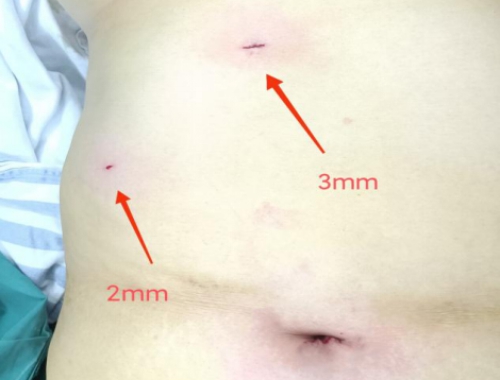

超微创术后画面

黄长文表示:“科室常规采用三孔法进行腹腔镜胆囊切除手术,配合皮内整形缝合技术,手术瘢痕已不太明显。但很多患者,尤其是年轻人,对手术切口有更高的要求。为此,医生在不增加手术风险和费用的前提下,为有美容要求的患者进行超微创腹腔镜胆囊切除手术或者隐瘢痕单孔腹腔镜胆囊手术。超微创术式保留了常规腹腔镜胆囊切除手术中上腹部的两个戳孔,利用特制器械,将两个戳孔直径都缩小到3mm,与一般穿刺针的针孔大小相差无几,愈合后更不容易看出手术瘢痕,美容效果更好。而单孔手术的瘢痕隐藏在脐孔,术后同样看不到瘢痕。”